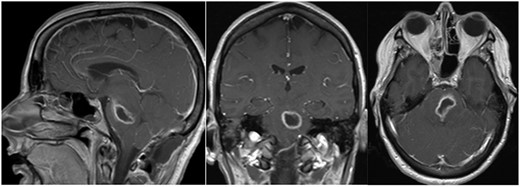

Post-op axial, coronal and sagittal T1 post-contrast MRIs demonstrating decrease size of rim enhancing pontine abscess.

Three days after initial presentation, she underwent sub-occipital craniotomy for microsurgical abscess drainage. Initial consideration was given to a stereotactic procedure; however, an open approach was ultimately chosen due to surgeon preference. Intraoperative neuro navigation was used with subsequent creation of a posterior fossa craniotomy. This approach was chosen over a retrosigmoid approach, given the midline nature of the lesion. The dura was opened over the right cerebral hemisphere and tonsil at which time pus was expressed and was cultured immediately at the operative site. We were unable to dissect the roof of the fourth ventricle secondary to a large volume of pus and instead retracted the bilateral tonsils and resected a small amount of the inferior vermis. Facial colliculus was localized and an incision was made in the midline medial raphae. Incision into the brainstem did not express any purulence, so the wound was copiously irrigated and subsequently closed without advancing further into the brainstem. Cultures from the abscess grew step intermedius and antibiotics were narrowed accordingly. Over the next several weeks, the patient remained afebrile with no leukocytosis, but there was concern for persistent infection due to lack of clinical improvement. Repeat MRI demonstrated enlargement of the residual abscess (Fig. 2a–c), and she was taken back to the operating room for repeat abscess drainage via the same sub-occipital craniotomy incision. During this procedure, the roof of the fourth ventricle was visualized and dissected through before localization of the vagal trigone. Midline raphae was once again opened and intraoperative MRI navigation confirmed the locations of the abscess. Microscopic dissection was performed in the midline between facial colliculi, and spinal needle was passed into the opening with subsequent aspiration of 9-ml purulent fluid, re-aspiration attempt and closure. Repeat gram stain and culture failed to reveal any organisms.